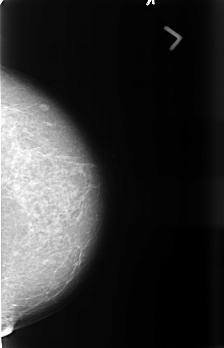

B_3441_1.LEFT_CC

LEFT_CC LINES 4512 PIXELS_PER_LINE 2904 BITS_PER_PIXEL 12 RESOLUTION 50 NON_OVERLAY